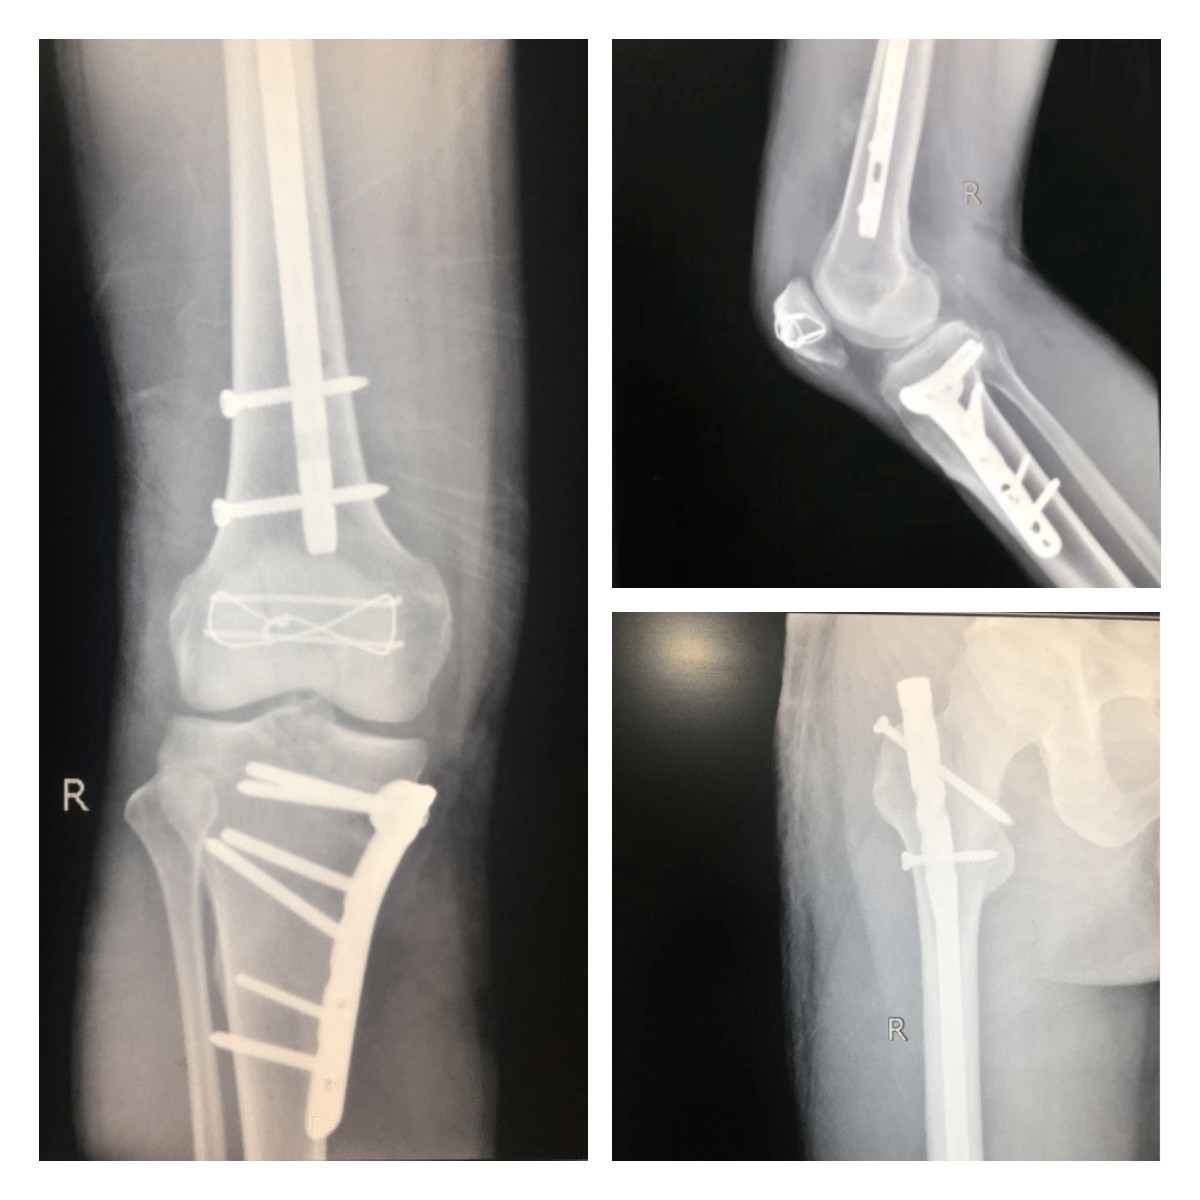

在宜宾民心创伤骨科医院骨科主任的带领下,团队迅速制定方案,完善术前检查,第一时间对患者进行了右股骨、胫骨上段、髌骨粉碎性骨折切开复位内固定手术治疗。